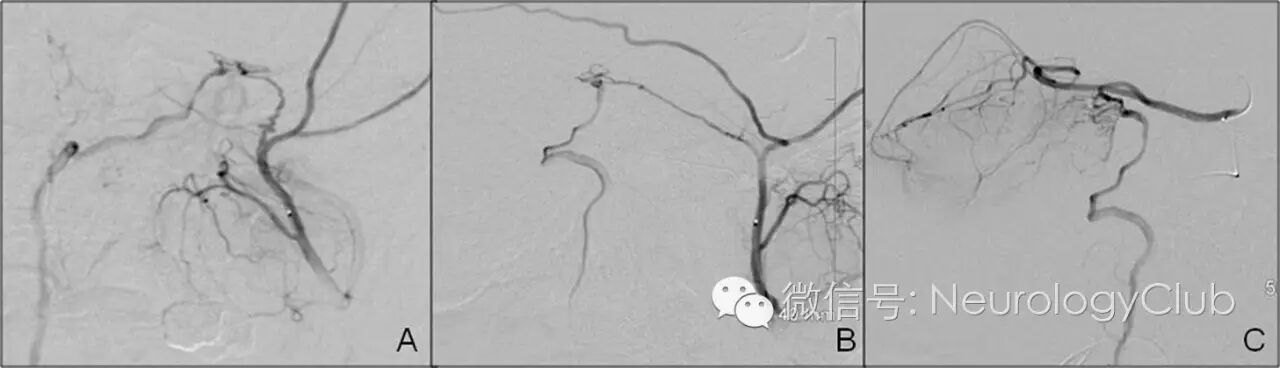

MRI提示弥漫颈髓肿胀以及脊髓前静脉扩张。这些改变提示颅内硬脑膜动静脉瘘(DAVF)伴髓周静脉引流,后经脑血管造影证实。该瘘的供血来自脑膜中动脉和左侧小脑上动脉(图2)。尝试Onyx栓塞脑膜中动脉不幸失败。改用Histoacryl经动脉栓塞左侧小脑动脉获得成功。1年后,患者可脱离工具轻松行走。MRI和脑血管造影可见脊髓水肿和DAVF消失(图3)。

(图2:A:脑血管造影侧面投影可见V型硬脑膜动静脉瘘由脑膜中动脉供血;B:椎动脉注射造影剂可见左侧小脑上动脉和扩张的左侧椎动脉;C:静脉分流和左侧小脑上动脉)